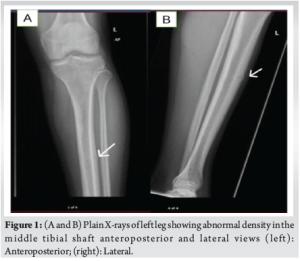

A 26-year-old male professional football player presented to us in the outpatient clinic in July 2024, on wheelchair with the complaint of bilateral shin pain over the past 4 months, localized on the anterior aspect of both legs. The pain was initially mild and worsened during playing football, followed by a constant pain on the left side, which started affecting his sleep and his routine activities. In addition, he complained of mild discomfort on his right leg. He had no history of any recent trauma and other joints or extremity pain in the past, but claimed an increase in intensity of pain while playing football. He had previously used anti-inflammatory medications, calcium, and activated cholecalciferol supplements, and underwent 8 sessions of physiotherapy. During physical examination, inspection revealed normal gait and normal alignment of both lower limbs and there was mild tenderness left mid leg and absent tenderness on the right side on palpation. The range of motion of associated joints and spine was within normal limits. Sensory and motor of each lower limb was normal and comparable. Plain X-ray of left leg (Fig. 1) demonstrated abnormal density in the middle left tibial shaft anteriorly, while right tibia X-rays were inconclusive. Based on X-ray results, the possibility of osteomyelitis in the left tibia was considered, and all inflammatory markers (C-reactive protein, erythrocyte sedimentation rate) were sent, revealing normal levels, which excluded any infections. In addition, endocrine/metabolic workup (Vitamin D, Calcium, parathyroid hormone, thyroid-stimulating hormone, and testosterone) was done and was in normal limits. A computed tomography (CT) scan confirmed left tibia anterior shaft stress fracture (Fig. 2). After reviewing the patient’s history, review of all medications, and thorough examination, including a careful biomechanical assessment and scanning results, a diagnosis of a stress fracture in the left tibia was made. Due to a lack of improvement with trial of conservative management on the left side over the past 4 months, a decision was made to proceed with intramedullary nailing on the left tibia while continuing conservative treatment on the right side, as the X-rays were unremarkable. Post-operative recovery of the patient was unremarkable, and he was allowed weight bearing as tolerated under the supervision of a physiotherapist (Fig. 3). At 3 months, he presented to the outpatient clinic as a follow-up case, with minimal symptoms in his left tibia. However, he expressed ongoing discomfort and mild pain in his right leg, which he claimed partly alleviated with analgesics and avoiding exertional activities. Due to ongoing pain on his right side, right leg X-rays were performed that revealed suspicion of anterior cortex stress fracture (Fig. 4). Consequently, an MRI was performed, which displayed a low signal on T2-weighted imaging with cortical thickening and bone marrow edema, confirming anterior tibial stress fracture (Fig. 5). Keeping in view his previous history, present imaging results and delayed diagnosis, he was decided to undergo intramedullary nailing right tibia. At the 4-month follow-up after the surgical fixation of his right tibial stress fracture, the patient was fully ambulant without any support. Follow-up radiographs of the right leg showed an evidence of fracture healing and nail in situ (Fig. 6). By 6 months, the patient returned to competitive football without restrictions.